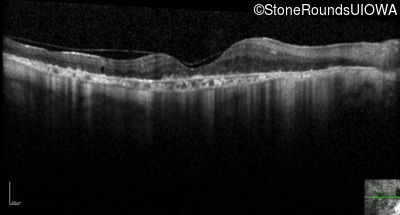

Optical Coherence Tomography - Left - 10/32 -2

Exemplar / OCT Stack

OCT Stack